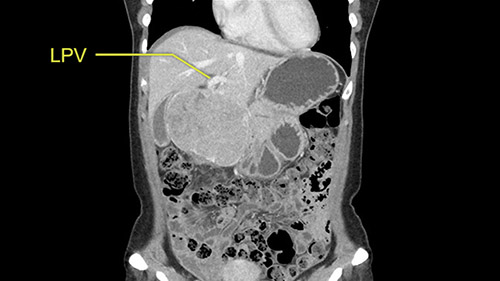

So if we look at the CT scan, on the axial, it’s a larger lesion. It’s about 6 or 7 or 8 centimeters. So it does look a bit threatening in terms of its resectability but if you really drill down deeply into the anatomy, and I think the coronal [imaging] is even better, you can see that the entire mass is on the patient’s left side of the falciform ligament. So it’s really only a left-sided tumor and not even really a left-sided tumor because Segment 4 is uninvolved anatomically.

As I review the CT scan, we have both arterial and venous phases, the tumor is obvious. But I’ll start by saying that the liver itself does not appear to be cirrhotic to my eye. It’s got a normal contour and allied to that, that I do not see evidence of portal hypertension. The spleen is normal, there’s no collateral vessels. The tumor itself, I measured maximally at about 11 centimetres in diameter and I’m told the alpha fetoprotein is very high (over 10000), which is entirely consistent with this being a solitary hepatocellular carcinoma that is very exophytic. It seems to emanate off the inferior margin of Segment 3 (because that’s the falciform). I’ll start by saying that this is not transplantable. The tumor exceeds our guidelines for transplantation, but it's likely resectable based on normal liver and no portal hypertension.

So the issue with regards to resection. A left sided tumor. I believe I can see the falciform ligament right here so we’re looking at a resection of Segments 2, 3 of the left lobe of the liver. The left portal vein is right there. I think we’ll be wiser to take the left portal vein and therefore get well into Segment 4 and do a left hemihepatectomy. Certainly, one does not need to take the middle hepatic vein; it’s miles from the tumor.

The other thing I would do in this case is to certainly to assess the coronal phase as we can see in the coronal phase, this tumor looks like it's growing from Segment 3, and again I don’t think there’s involvement of the right side of the liver or even on Segment 4.

La decisión aquí, y otra vez mirando, me parce importante mirar a los cortes coronarios porque parece que este tumor cuelga del segmento tres y aquí la cuestión va a ser si vamos a realizar una resección más limitada y hacer una recesión del segmento tres, o si vamos a tener que realizar una hepatectomia izquierda. En cuanto a puntos importantes en ambas opciones, en todos los casos vamos a intentar realizar un recesión anatómica ya que hay datos en la literatura que parecen indicar que una resección anatómica tiene mejores resultados oncológicos comparado con una recesión no anatómica; entonces realizaremos una resección del segmento tres y en este caso trataremos de buscar el pedículo que va al segmento tres, en este caso probablemente sea una resección del segmento tres, realizare una maniobra de Pringle y clampare el hilio para evitar el sangrado.